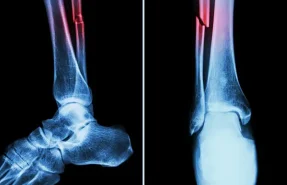

درمان شکستگی‌ها و دررفتگی‌ها

شامل بی‌حرکت‌سازی، جااندازی و در موارد شدید جراحی  است. هدف ترمیم استخوان و بازیابی عملکرد مفصل است.